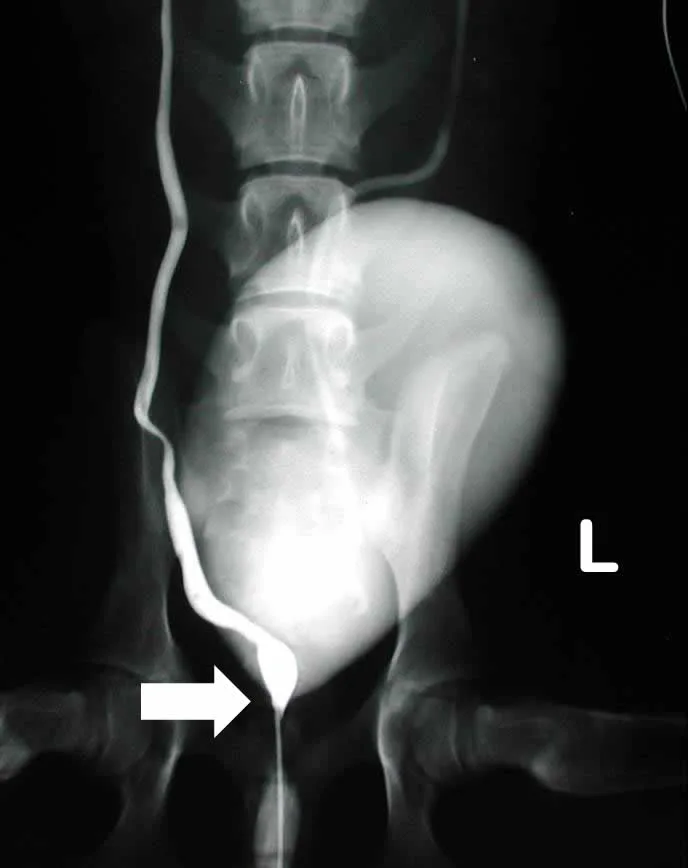

Contrast Radiography

A normal terminal ureter has a “J” shape as it enters the bladder, whereas an EU will frequently course straight caudally beyond the bladder (Figure 1, arrow). This indicator provides the correct diagnosis in about three quarters of cases.